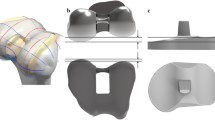

Three tibial insets with different designs are developed. We investigated the articular conformity of conventional conforming CR TKA in the Genesis II Total Knee System (Smith & Nephew Inc., Memphis, TN, USA) and for Evolution Medial Pivot Total Knee Arthroplasty (Wright Medical Technology, Arlington, TN, USA). In order to investigate the conformity of CR TKA, scanning with a non-contact 3D laser scanner (COMET VZ; Steinbichler Optotechnik GmbH, Neubeuern, Germany) with a 50-μm accuracy is used. The scanned point data are converted into 3D models, and scanning is repeated until the 3D model dimensions exhibit geometrical errors of < 100 μm [28].

The ratio of the curvature radius for the tibial insert to the curvature radius for the femoral component is investigated for conformity in the coronal and sagittal planes. A tibial insert with a conforming design of conventional CR TKA conformity (Genesis II) and a medial pivot tibial insert with medial pivot conformity (Evolution) are developed by applying the curvature radius ratio in the coronal and sagittal planes to the patient-specific femoral component (Fig. 2). An anatomy tibial insert is developed using a patient’s tibial curvature and is similar to the femoral component. The bone coverage exceeded 95% in the patient-specific TKA, irrespective of differences in the insert design (Fig. 2). All of the femoral component designs in the patient-specific TKA are identical.